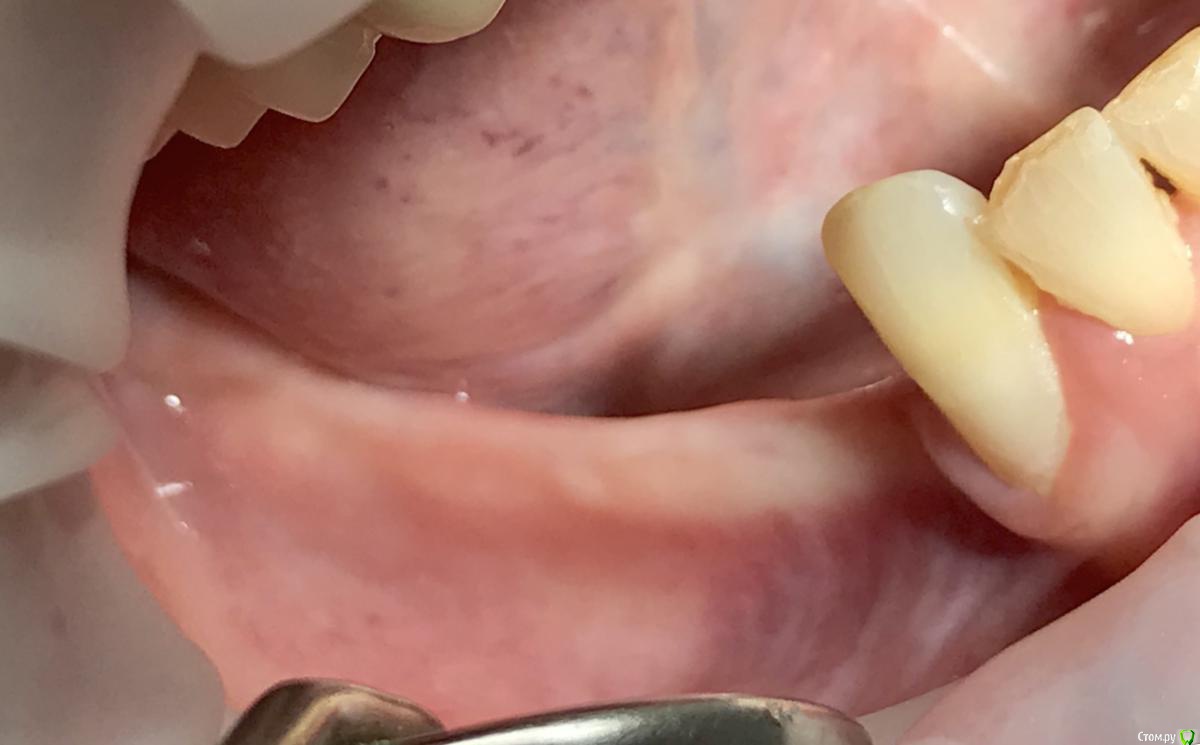

EEcho Опубликовано 16 ноября, 2018 Поделиться Опубликовано 16 ноября, 2018 Коллеги, добрый день!Ваши варианты при такой атрофии. Ссылка на комментарий

EEcho Опубликовано 22 ноября, 2018 Автор Поделиться Опубликовано 22 ноября, 2018 Это понятно, что можно любую методику кроме расщепления и моноблоков, но как в этом случае обойти ментальное отверстие с выходом сосудисто-нервного пучка почти вертикально? Резать мембрану обходя отверстие и бить кнопки вокруг, то есть сосиську по Урбану, с эволюшкой.? или делать каркас из мини пластин.? полужестким каркасом отверстие будет не обойти.( возможно графт будет через него высыпаться или врастет через него соединительная ткань)? Ссылка на комментарий